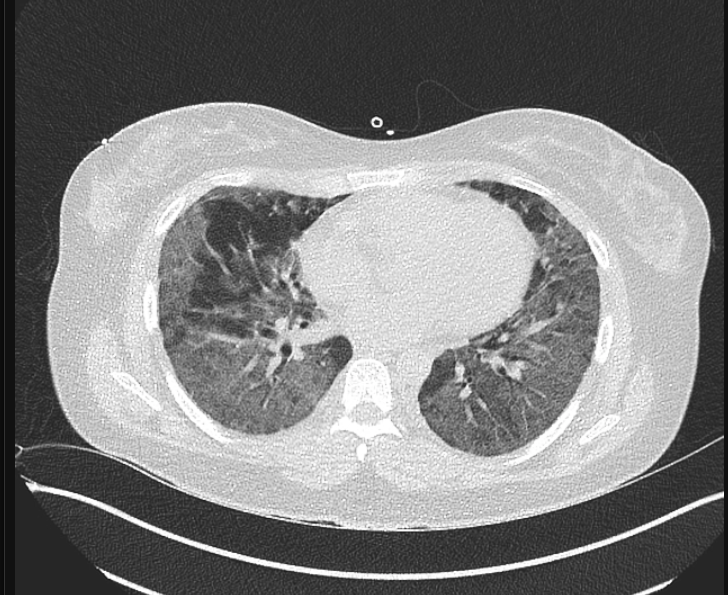

80 Mulher, Tosse

Consolidação com cavitação em lobo superior direito

Adenocarcinoma